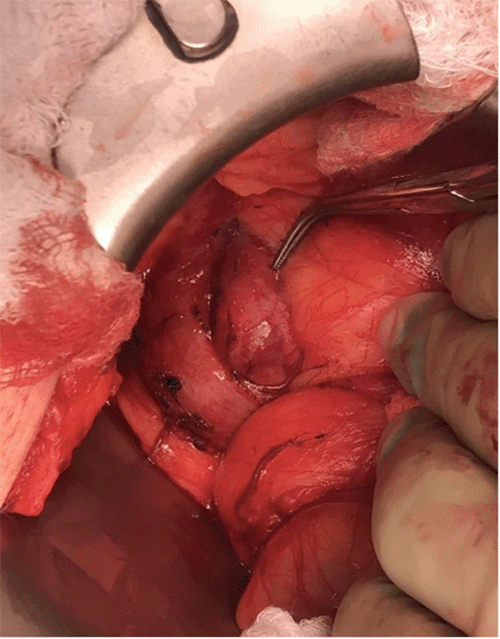

Our patient is a 62-year-old female who initially presented to an outside physician with complaints of vague abdominal pain. This was initially attributed to symptomatic cholelithiasis, and she underwent robotic cholecystectomy with no improvement in her symptoms. Given the persistence of her symptoms, her primary care physician obtained computerized tomography (CT) of the abdomen. This imaging revealed a lesion of the pancreatic head and prompted a subsequent referral to our service for evaluation. On her initial presentation to our team, she described several other symptoms besides her pain, including facial flushing, night sweats, nausea, diarrhea, and weight loss. Her above-described imaging revealed a 2.4 × 2.0 × 3.0 cm well-circumscribed nodular enhancing mass of the pancreatic head adjacent to the duodenum (Figure 1). An incidentally found 2.1 × 1.8 cm adrenal nodule was subsequently biopsied (following negative biochemical testing for pheochromocytoma) and found to be without malignancy.

Figure 1. Computerized Tomography of Abdomen. Published with Permission

Image depicts well-circumscribed nodular hypervascular enhancing mass of the pancreatic head, later found on surgical pathology to represent nonfunctional neuroendocrine tumor of the pancreas